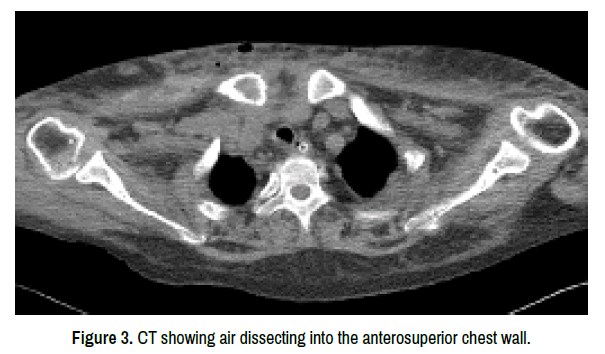

On the afternoon of the fifth day, patient presented diffusing blue-purple ecchymosis over the bilateral inguinal regions. A matter of considerable concern was the observed drop in hemoglobin level and blood platelet count, which worsened to 71 and 50 respectively. The results of coagulation function test at this time showed an ascend except descending thrombin time hence decided to transfuse 2 units of packed cells and human albumin. As her hospitalization progressed, the right side of her chest and left upper limb had draining openings with a necrotic appearance associated with a foul smell (Figure 2). Multiple bullae and small blisters around necrotic area were noted. The clinical picture and CT findings (Figure 3) confirmed the diagnosis of necrotizing fasciitis. The patient underwent aggressive bedside wound debridement of the necrotic tissue exposing the contents and packed open with BIPP dressing. The clinical course was complicated by septic shock, acute respiratory distress syndrome and acute renal failure. Despite aggressive medical and surgical intervention, the patient expired from multisystem organ failure on day twenty.

clinical-case-reports-anterosuperior

Figure 3. CT showing air dissecting into the anterosuperior chest wall.